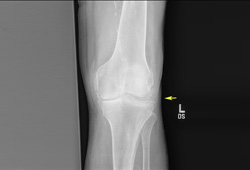

Plain x-rays of the affected joint can be helpful diagnostically.[46] Cartilage calcification can be seen in small joints, but patients with suspected polyarticular CPPD should have x-rays of the knees, pelvis, and wrist. These films have the highest likelihood of revealing radiographical cartilage calcification.[47] Plain x-rays can also rule out fractures, lytic bone lesions, and changes consistent with erosive rheumatoid arthritis. [Figure caption and citation for the preceding image starts]: Knee x-ray with linear calcific deposits of cartilage calcificationFrom the personal collection of Ann K. Rosenthal, MD [Citation ends].